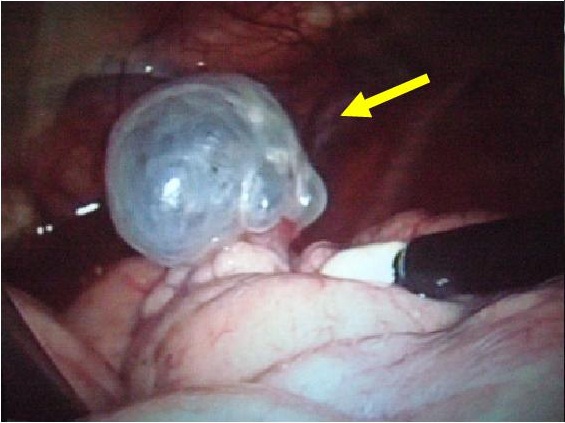

自然気胸の術中所見

肺嚢胞からの空気漏れ

肺嚢胞の結紮

術中写真自動縫合器による肺嚢胞(ブラ)切除(肺部分切除)

肺嚢胞

自動縫合器による肺切除

肺切除後の状態

ネオベールシートによる胸膜補強